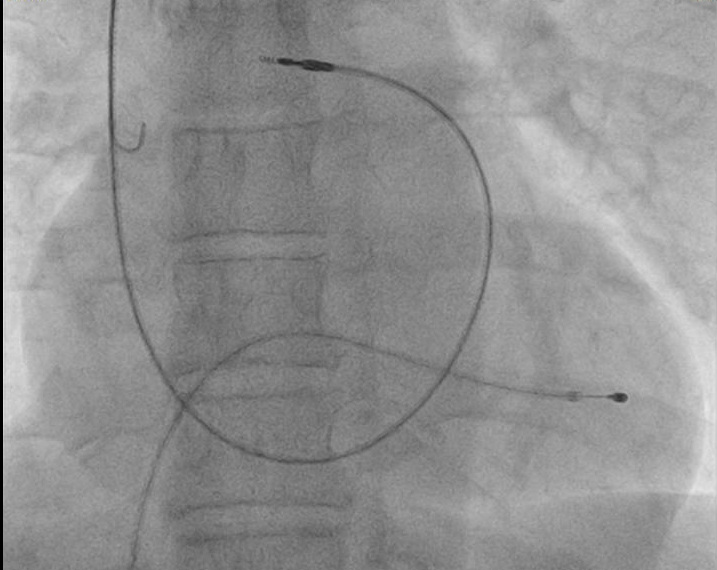

Ventricular lead placement

RVA placement

• Gently curved stylet

• Straight stylet

• RVOT -> RVA

RVA

pa_postion.jpg

passive_rva.jpg